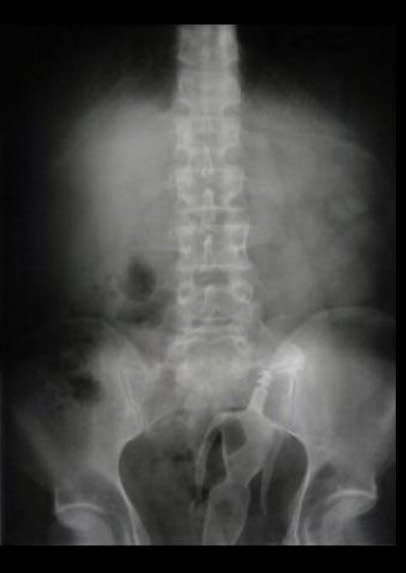

regardez moi ça 

(Le premier c'est pas un concombre , c'est une courgette, le 3eme c'est une lampe torche)

Quelqu'un a t il perdu ses clés ?